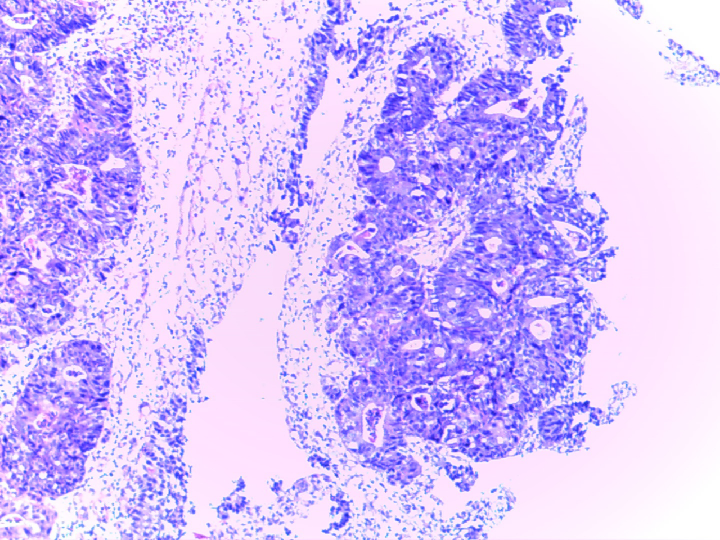

病理:(乙状结肠)腺上皮癌变。

2020-02-13 术后病理

(降结肠切除标本):腺癌,中分化,溃疡型,癌组织浸润至浆膜层,见脉管内癌栓,神经见癌组织侵犯,标本上、下切缘未见癌组织残留。隆起:管状腺瘤伴低度上皮内瘤变。肠系膜查见淋巴结6枚未见癌组织转移,癌结节6枚。另见肠管壁:肠粘膜慢性炎伴局灶浅表溃疡形成,粘膜下层血管扩张、充血。

[IHC:2020069]PCK(+);Ki-67约30%+;P53(-);CDX-2(+);EGFR(±);VEGF(-);MLH1(+);MSH2(弱+);MSH6(+);PMS2(弱+)。